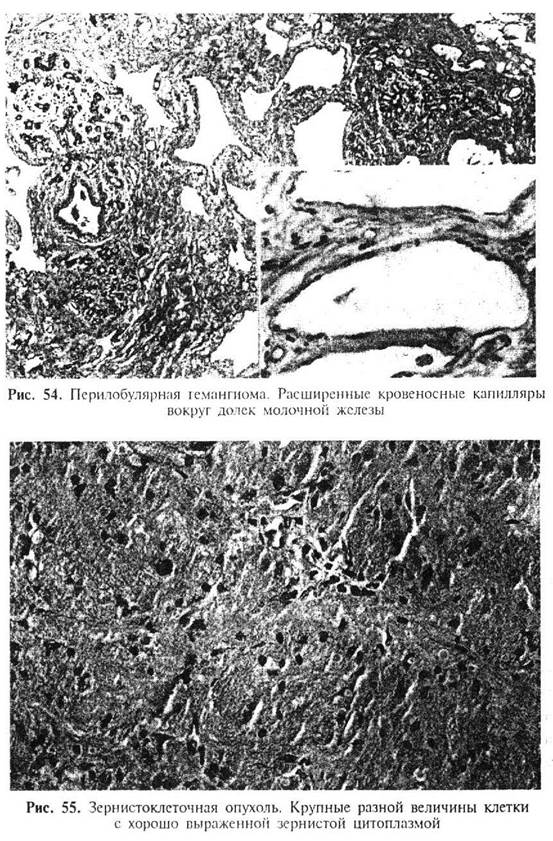

Перилобулярная гемангиома (рис. 54) обычно определяется только микроскопически и характеризуется расширенными капиллярами вокруг долек молочной железы.

Зернистоклеточная опухоль (миобластомиома, опухоль Абрикосова, миобластома) - доброкачественное образование, которое может иметь клинические и макроскопические проявления инвазивного рака молочной железы. Обычно опухоль имеет малые размеры, но может достигать 10 см и более. На разрезе опухоль четко очерчена, прочно связана с окружающими тканями молочной железы, имеет плотную консистенцию, равномерный белый или серовато-желтый цвет. Микроскопическое строение (рис. 55) изложено в соответствующих разделах руководств, посвященных опухолям мягких тканей. Выявляется крайне редко, характеризуется доброкачественным течением.